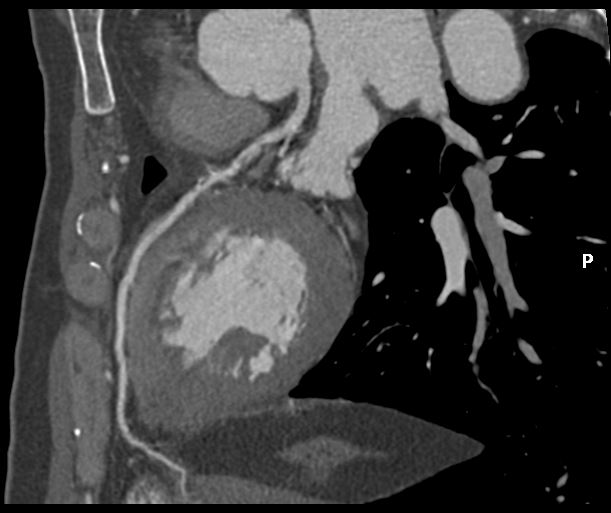

Echocardiogram showed good left ventricular ejection fraction of 53%. A multislice computed tomography coronary angiogram (MSCT-Coronary) demonstrated severe stenosis involving the proximal left anterior descending (LAD),proximal left circumflex (LCx),and proximal right coronary artery(RCA).The patient was subsequently admitted electively for diagnostic coronary angiography and possible percutaneous coronary intervention (PCI).

Angiographic assessment showed a normal left main stem, with severe proximal LAD disease exhibiting moderate calcification and providing retrograde collateral supply to both RCA and LCx. The LCx demonstrated severe mid-segment disease with subtotal occlusion of the obtuse marginal 1 (OM1) branch. The RCA showed severe proximal disease and total occlusion of the posterolateral(PL) branch.